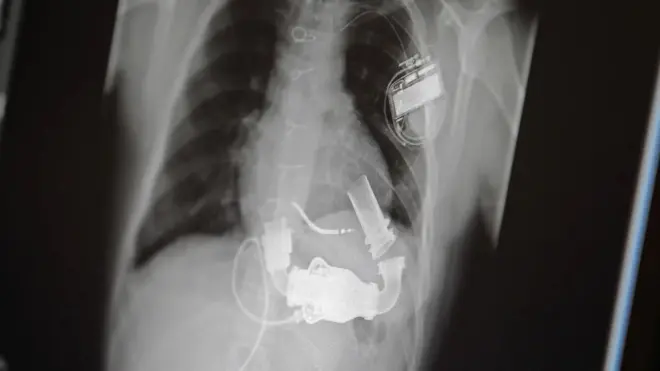

Hatimaye siku kama hiyo ilifika. Mnamo Februari mwaka jana, Anthony alikua mtu wa kwanza ulimwenguni kupandikizwa viungo vitatu - moyo, ini na figo - kupitia mbinu inayoitwa BRN (normothermic regional perfusion).

Wafadhili kama hao ni watu walio na ugonjwa wa ubongo usioweza kupona ambao huwekwa hai kwa msaada wa mashine ya kuwezesha kupumua.

Kabla ya kutoa viungo vya watu kama hao, madaktari lazima wapate ruhusa kutoka kwa familia zao.

Kisha mashine ya kumsaidia mgonjwa kupumua huondolewa na matokeo yake, moyo na mapafu ya mtu huacha kufanya kazi na baada ya dakika tano mtu hutangazwa kuwa amekufa.

Kisha daktari hutumia mashine kuingiza damu ndani ya mwili wa mtu aliyefariki ili kujaribu kufanya moyo na mapafu kufanya kazi tena.

Utaratibu huu hutumika kuangalia kama moyo wa mgonjwa unafaa kwa kupandikizwa au la.

Mchakato huu hufanyika mbio mbio dhidi ya muda, hivyo basi mchakato mzima unafanywa haraka iwezekanavyo.

Dkt. akizungumza na BBC, Nader Mozmi alisema kuwa mtu akifariki kwa ugonjwa wa moyo au mapafu, njia bora ya kujua iwapo moyo wake unafaa kwa upandikizaji ni kurejesha mzunguko wa damu wakati kiungo hicho kikiwa mwilini.

Mozami, ambaye anafanya kazi kama mkurugenzi wa upasuaji wa upandikizaji wa moyo na usaidizi wa mitambo ya mzunguko wa damu huko NYU Langone Health, pia alisema kuwa tangu aanze kutumia mbinu hiyo mnamo 2020, mioyo iliyoonekana kuwa haifai kwa upandikizaji haijatumika.